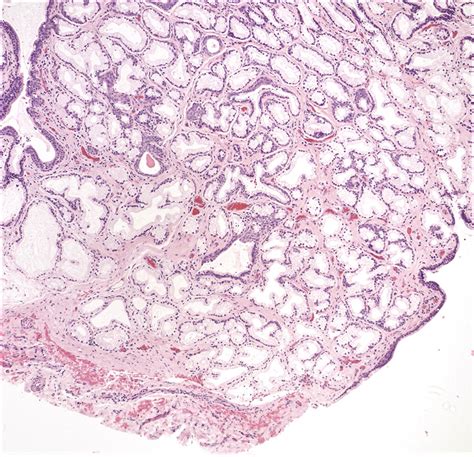

What is a Skene’s Gland Cyst?

A Skene’s gland cyst is a fluid-filled sac that forms within the Skene’s glands. These cysts can vary in size and may cause discomfort or other symptoms. The exact cause of Skene’s gland cysts is not always clear, but they are often associated with infections, blockages, or inflammation in the glands. Understanding the underlying causes can help in managing and treating the condition effectively.